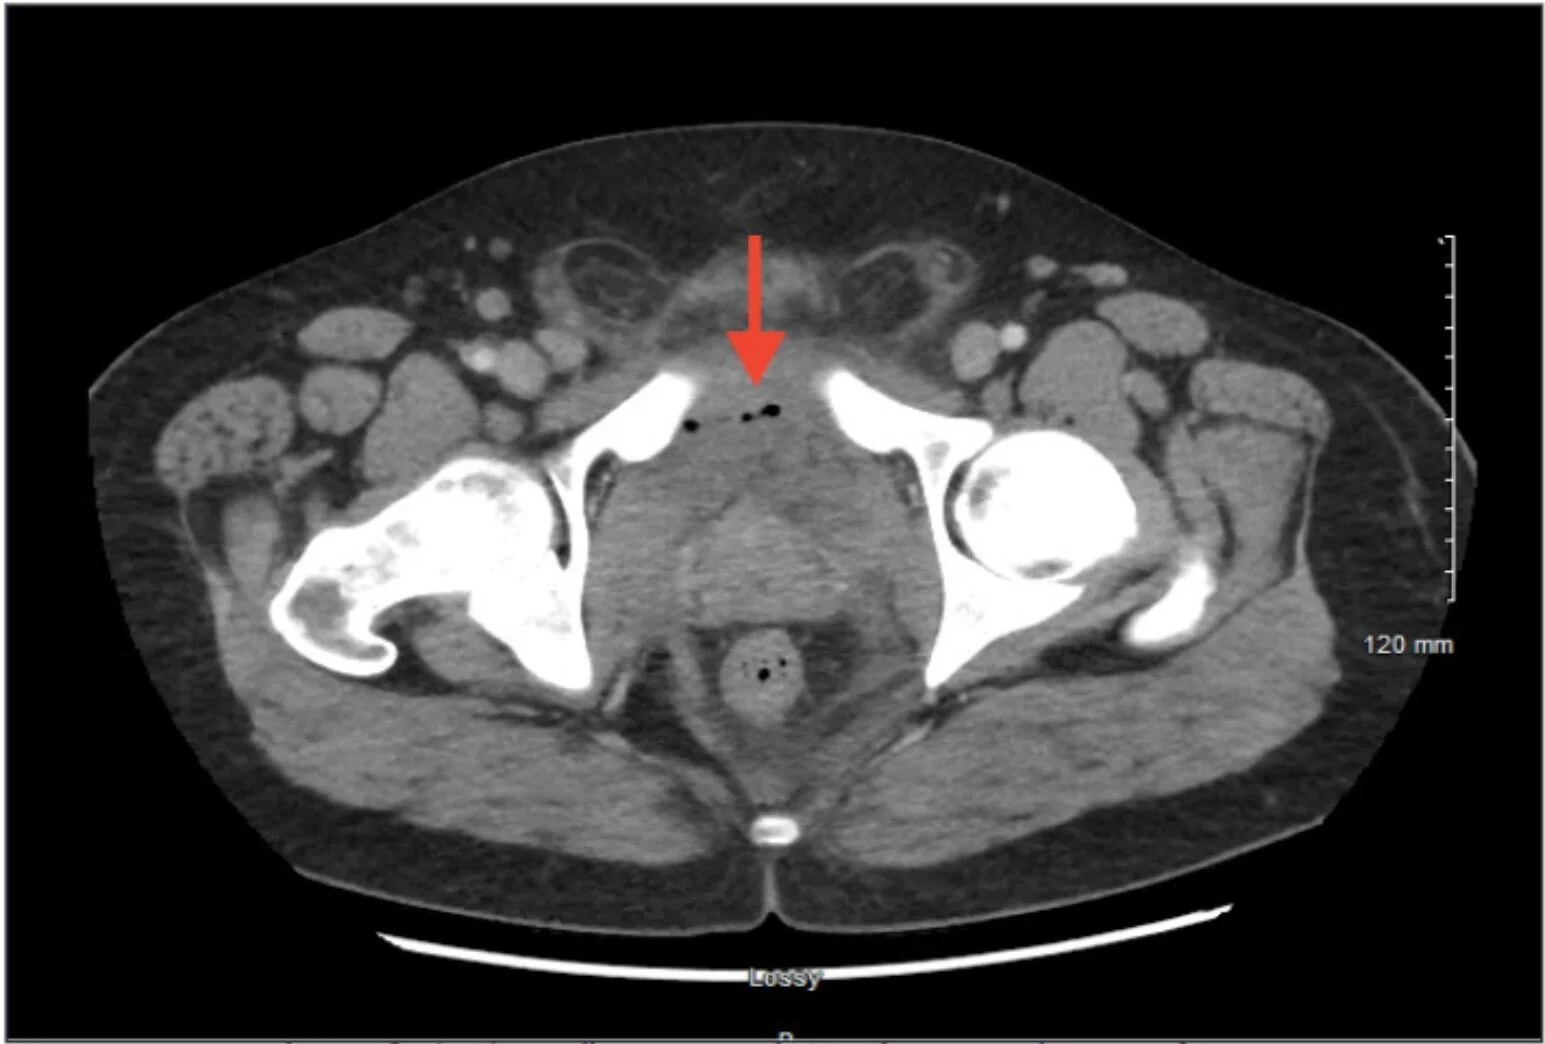

The patient’s history of IVDU, tachycardia, leukocytosis, and elevated inflammatory markers (ESR, CRP) with severe inguinal pain and dysuria were concerning for a pelvic or intra-abdominal infection. This was confirmed by CT, as the CT demonstrated a retropubic abscess secondary to septic arthritis of the pubic symphysis (see Image 1). The patient was started on vancomycin and ceftriaxone after blood cultures were drawn, and the orthopedics service was consulted for management. They recommended admission and interventional radiology consultation to percutaneously drain the extraperitoneal fluid collection.

example image showing APPROXIMATELY a 5 CM FLUID & GAS COLLECTION ON AXIAL CT IN THE PREVESICULAR SPACE OF RETZIUS

The test of choice for diagnosis of abscess in the space of Retzius in the ED is a CT of the abdomen and pelvis with IV contrast. This will also assist with evaluation of septic arthritis or osteomyelitis of the pubic symphysis and will evaluate for other intra-abdominal abscesses or fluid collections. MRI is another potential diagnostic modality to evaluate for osteomyelitis and adjacent abscess, although it is typically less available in the standard emergency department compared to CT.